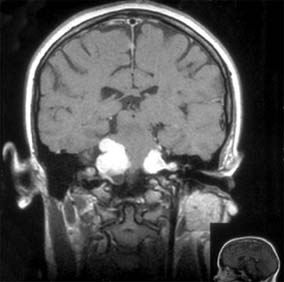

PITUITARY TUMORS

The anterior lobe of the pituitary gland is the site of origin of pituitary tumors (Figure 14-26). Symptoms and signs include loss of vision, field changes, pituitary dysfunction, extraocular nerve palsies, and evidence on CT scan or MRI of sellar and suprasellar tumor.

Figure 14-26

Figure 14-26: Coronal MRI showing large pituitary adenoma elevating and distorting the optic chiasm.

Combination therapy with radiation and surgery has been challenged by medical treatment with bromocriptine, which has been effective not only in tumors associated with galactorrhea but also in some null cell (or endocrinologically inactive) tumors. Visual loss or endocrine dysfunction is an indication for treatment. Visual acuity and visual fields may improve dramatically after pressure has been removed from the chiasm. The initial appearance of the optic nerve head does not predict the ultimate visual outcome.